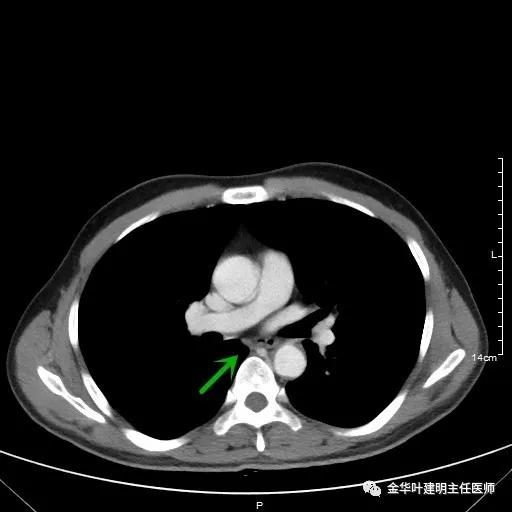

如果选取肿瘤所在的层面来看,则是以下图像:

以上是肺窗,见右肺下叶实性占位,有毛刺、浅分叶、膨胀性,血管征等,是较为典型的恶性肿瘤。

以上为纵隔窗,可见纵隔内未见显著增大的转移性淋巴结。